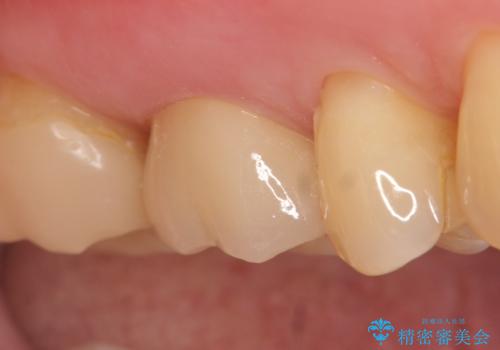

オールセラミッククラウン 根管治療後の補綴

オールセラミッククラウン(エコノミー)はスタンダード以上と違い、一塊となっているため欠けてしまうリスクが低いのが特徴です。

しかしその反面選択できる色の種類が少なく、色合いも単調であるという欠点もありますが、今回のケースのように前後の歯がクラウンの場合などでは十分に審美的な補綴が可能となります。